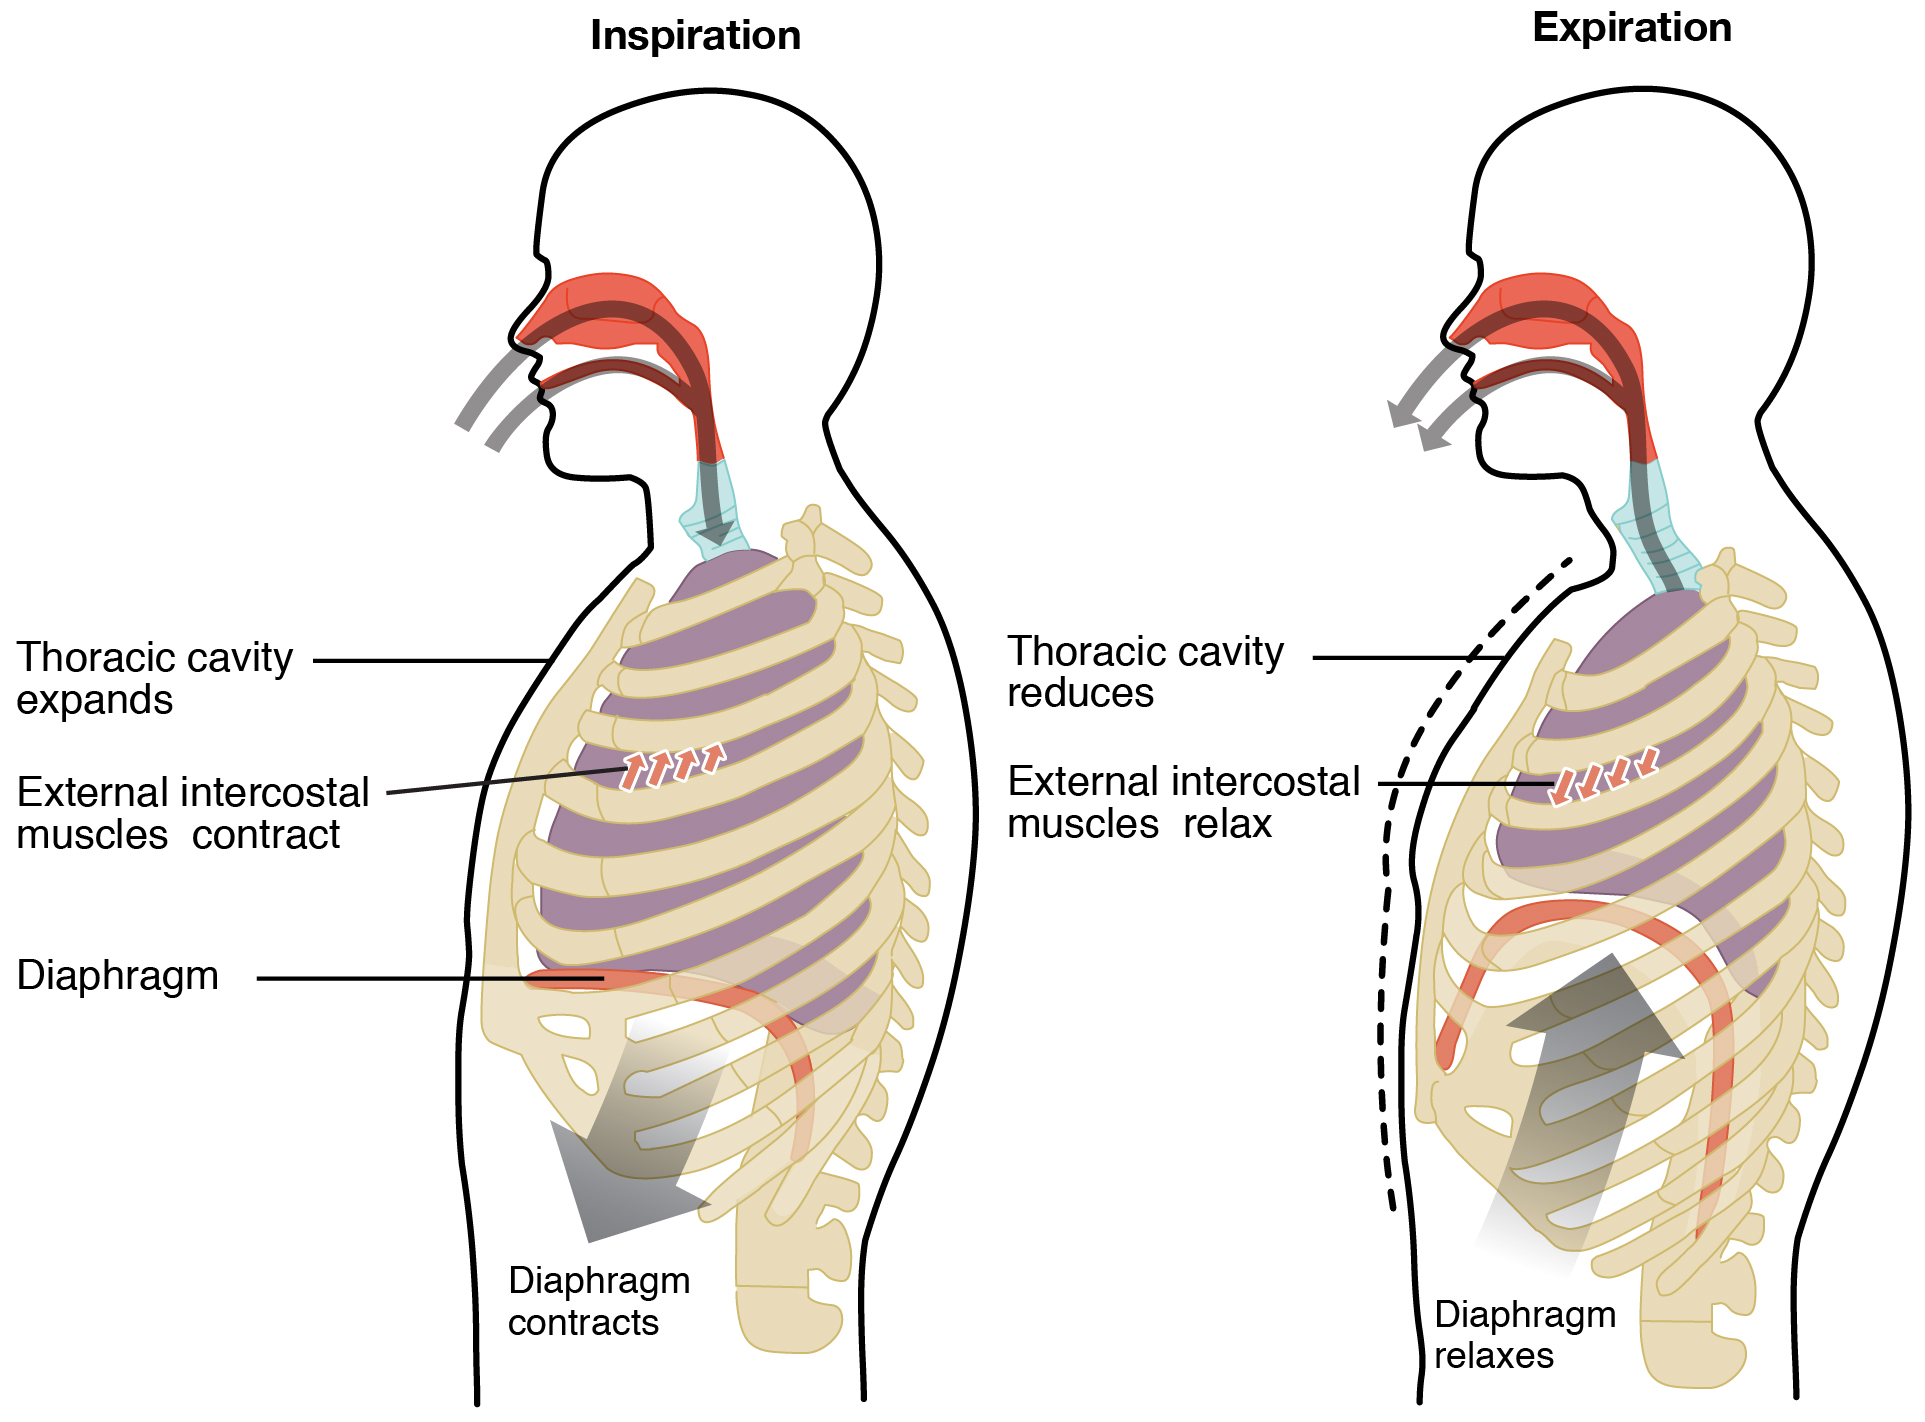

Normal Difference Between Chest Inspiration And Expiration

Normal Difference Between Chest Inspiration And Expiration

More picture related to Normal Difference Between Chest Inspiration And Expiration

Mechanism Of Breathing As Anatomical Process Explanation Outline

Mechanism Of Breathing As Anatomical Process Explanation Outline

Normal Difference Between Chest Inspiration And Expiration - 2025 DIY